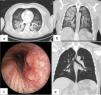

We report a case of a 38 years old male, smoker, without previous known pathologies and any assumed toxic habits. Pre-operative tests including coagulation, were normal. He was submitted to supraspinatus raffia through shoulder arthroscopy, under balanced general anesthesia with inhaled Sevoflurane. Orotracheal intubation (OI), performed with Macintosh laryngoscope, was smooth and easy with a 7.5mm reinforced tube. No trauma or other complications were reported during OI or surgery. Two minutes after extubation, the patient presented laryngospasm, desaturation, and massive hemoptysis. He was immediately reintubated and admitted to Intensive Care Unit, where a first diagnostic bronchofibroscopy was performed, reporting distal massive hemorrhage without any visible focus or trauma in the airways. Thorax Computed Tomography showed diffuse alveolar hemorrhage (DAH) and excluded pulmonary embolism (PE). After five days with OI, a new bronchofibroscopy showed a lesion in the posterior wall of trachea. An autoimmune screening was performed and excluded vasculitis. Patient was discharged after two weeks and a third bronchofibroscopy was made after one month, displaying good evolution.

In this case there were several different diagnostic possibilities: Airway trauma, PE, autoimmune diseases, negative pressure pulmonary edema (NPPE) and Sevoflurane induced DAH. The lesion found in the second bronchofibroscopy was not seen in the first exam, which could be related to the use of high pressure endotracheal cuff, during the five days of OI. In the other hand, in the first bronchofibroscopy, the presence of an orotracheal tube may have hindered the observation of tracheal trauma. NPPE after an upper airway obstruction such as laryngospasm is another plausible hipothesys.1 Still, preexisting pulmonary damage from smoking and administration of the irritating inhaled anesthetic Sevoflurane, could lead to DAH.1 There are, in literature, a few case reports1,2 of hemoptysis related to the association of inhaled Sevoflurane and NPPE after extubation, and this might be another one (Fig. 1).